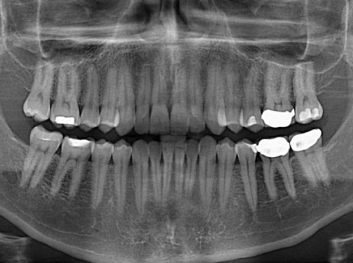

損壞的牙齒如何自我修復?近日,來(lái)自哈佛大學(xué)和諾丁漢大學(xué)的研究人員研發(fā)了能夠刺激牙齒干細胞再生的新型生物材料,而這種新材料研發(fā)成功的背后,正源于他們對牙齒如何實(shí)現自我修復這個(gè)課題的不斷探索。

據美國期刊《大眾科學(xué)(Popular Science)》報道,此種新型生物材料,不僅可以有效地取代傳統補牙填充物,刺激牙齒干細胞再生,患者也有望無(wú)需再接受根管治療,使蛀牙患者免除牙根感染或牙髓壞死的苦惱,一個(gè)全新的牙齒治療時(shí)代即將來(lái)臨。

Adam Celiz,是來(lái)自諾丁漢大學(xué)的研究人員,他和同事開(kāi)發(fā)的這種新型合成生物材料,能刺激干細胞在牙髓部的生長(cháng)。與普通材料一樣,這種合成材料被填充到牙齒并用UV光硬化。

在體外測試中,材料刺激干細胞進(jìn)入牙本質(zhì)的增殖和分化速度,促進(jìn)形成牙齒骨組織。研究人員認為,一旦材料在受損牙齒中應用,這些干細胞可以自動(dòng)修復來(lái)自填充物上的損壞。在本質(zhì)上,該生物材料將使牙齒自愈。

在未來(lái),Adam Celiz說(shuō),可再生材料能制成各種填充物以便受損牙齒的自身治愈,降低補牙失敗率,甚至會(huì )消除大部分人對根管治療的需要。